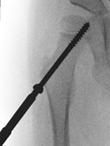

Guided growth uses remaining growth potential to gradually correct hip deformity with temporary minimally invasive transphyseal fixation. In this study we analyse guided growth in children with a full range of underlying disorders, including neuromuscular, developmental and growth disturbances.